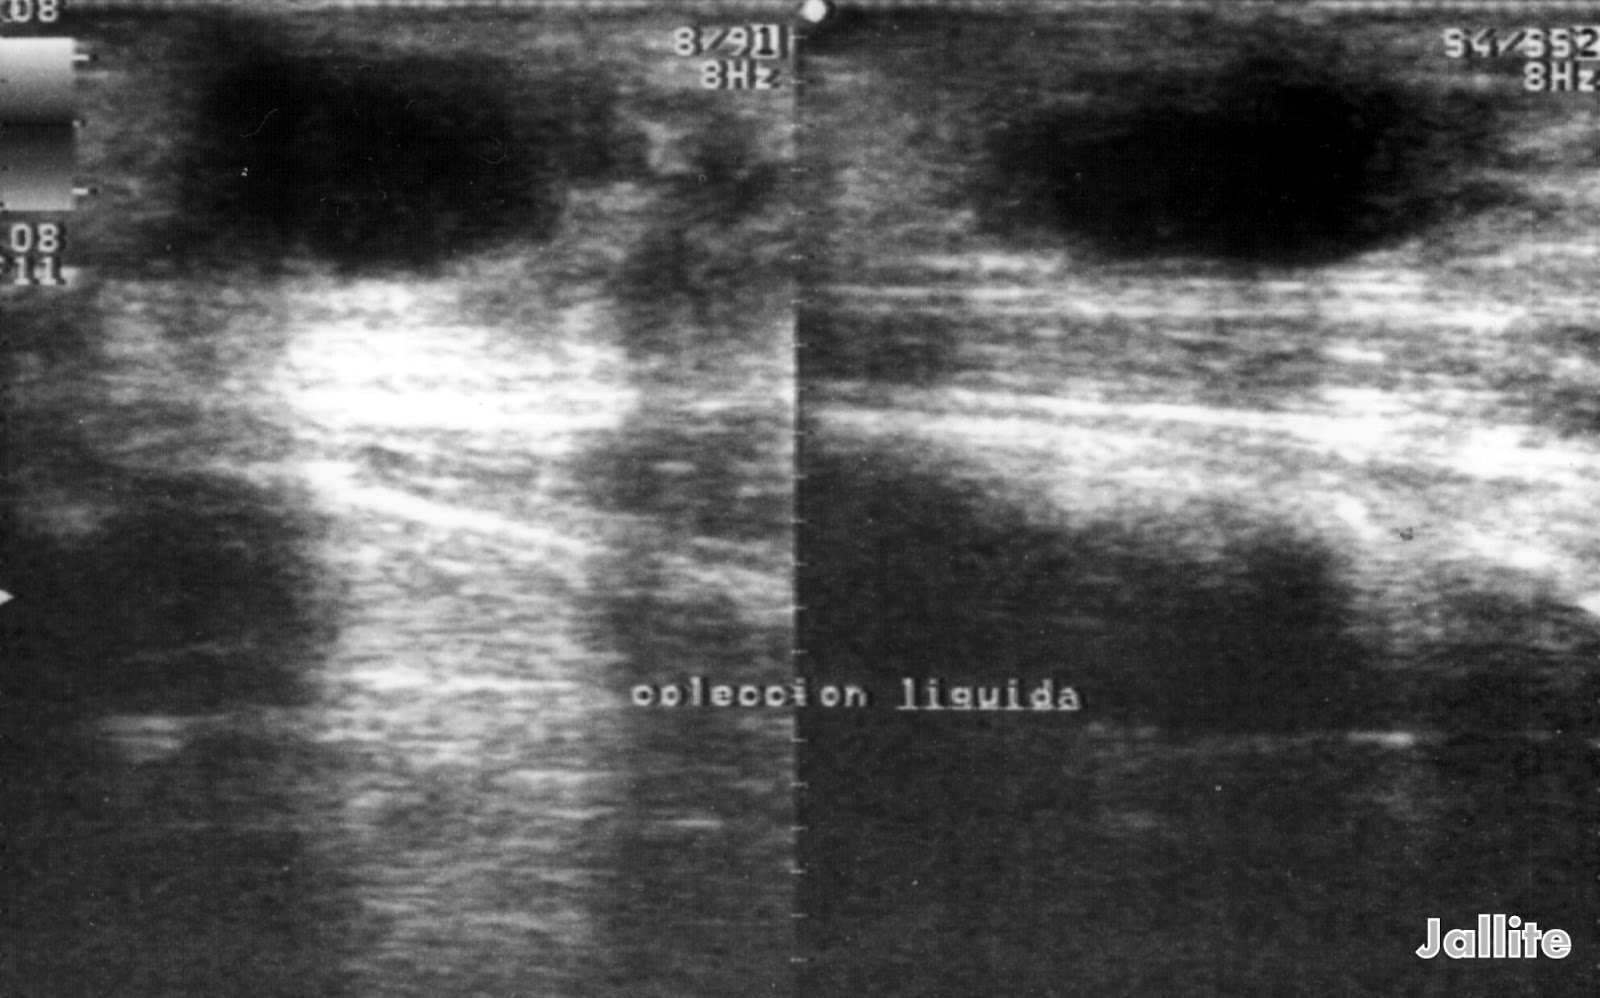

From diariodeunmedicoii.blogspot.com

Seroma Can You Put Heat On A Seroma A seroma is a buildup of clear fluid under the skin. — if the seroma becomes infected, it may appear red and feel very tender and warm to the touch. This article examines seroma treatment to. It most often occurs after surgery, but it can also happen due to injury. Not only will it improve drainage and reabsorption, but. Can You Put Heat On A Seroma.